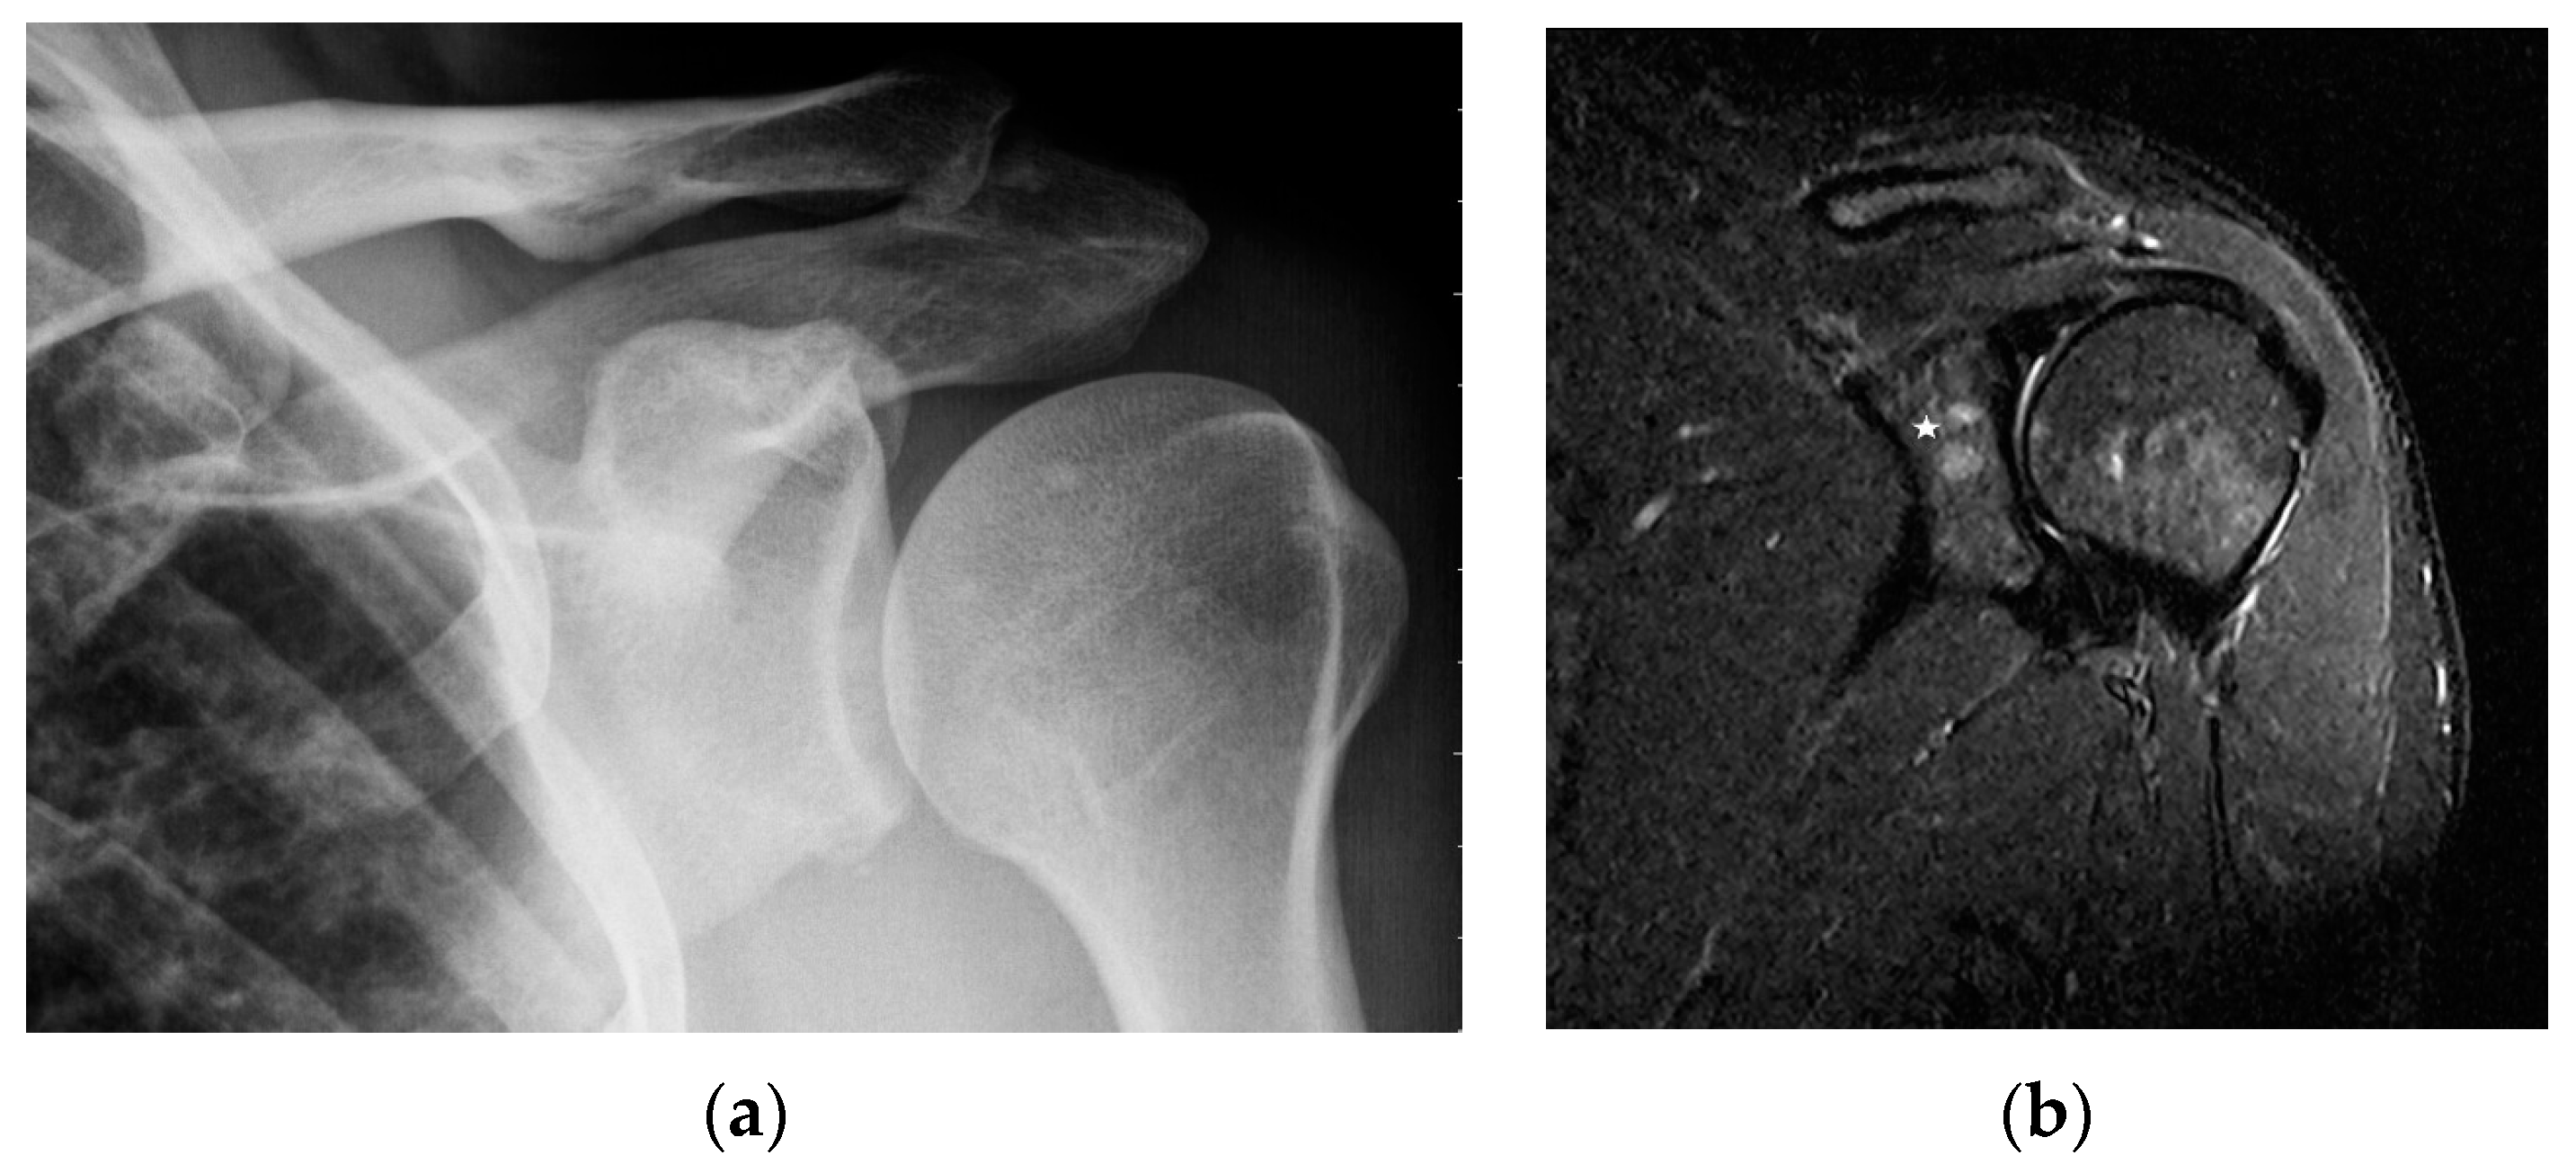

MR is a highly sensitive imaging modality that can detect bone marrow involvement in sarcoidosis. It also provides the detailed information on soft tissue involvement, synovitis and joint inflammation. Occasionally, MR images detect clinically and radiologically silent lesions (Figure 3a,b).

Figure 3. Radiograph (a) and magnetic resonance of the shoulder joint. T1-weighted image with fat saturation and with contrast administration (b). 40-year-old patient with sarcoidosis. Two contrast-enhanced lesions in the acetabulum of the joint ((b), asterisk) not visible on X-ray (a).